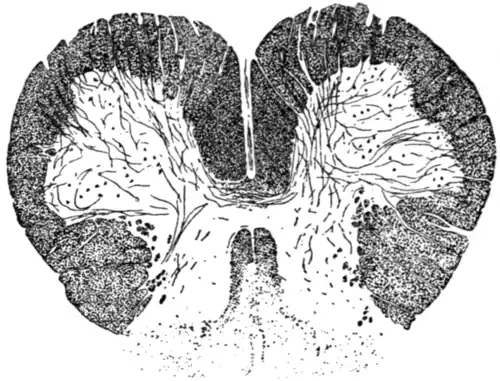

Fig. 8.—Diagram of section of the spinal cord in the upper cervical region, showing recent degeneration of the crossed pyramidal tract of the right side and direct pyramidal tract of the left side. The black dots indicate the degenerated fibres stained by the Marchi method. This degeneration is secondary to haemorrhage into the internal capsule of the left hemisphere, and it will be observed by the number of degenerated fibres that the greater bulk have crossed over to the right side of the spinal cord, thus agreeing with the fact that the paralysis is of the right half of the body. |